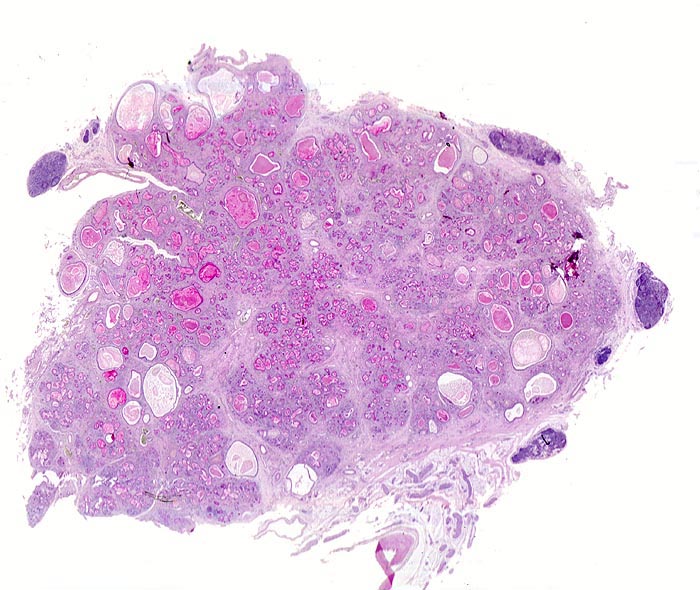

Morphologie:

Fast alle exokrinen Drüsen sind betroffen. Pankreasgänge, intestinale Drüsen, intrahepatische Gallengänge und die Glandula submandibularis sind obstruiert durch visköses oder solides eosinophiles Material. Tracheobronchiale und Brunner’sche Drüsen bilden vermehrten Schleim. Schweissdrüsen, kleine Speicheldrüsen und Glandula Parotis sind histologisch normal, sezernieren aber vermehrt Natrium und Chlorid. Veränderungen in der Lunge ( 3689) entwickeln sich als Folge von Luftwegsobstruktion und Infekten (initial vor allem mit Staphylococcus aureus, später meist Pseudomonas aeruginosa).